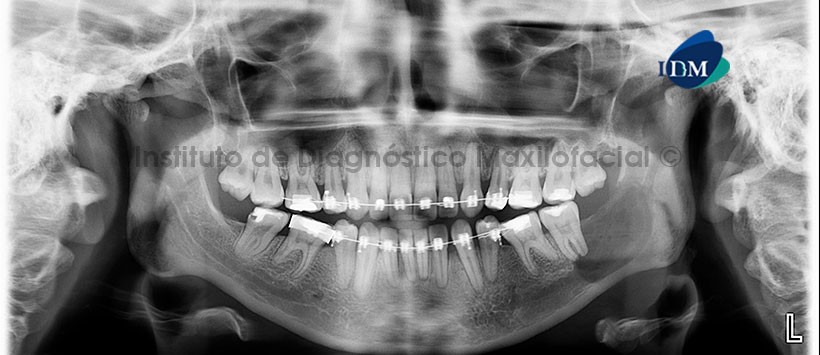

A la evaluación de la radiografía Panorámica de seguimiento a los 5 meses (Figura 2) se observa que la lesión tuvo un leve aumento en el tamaño, ocasionando el adelgazamiento y desplazamiento de la cortical basal mandibular.